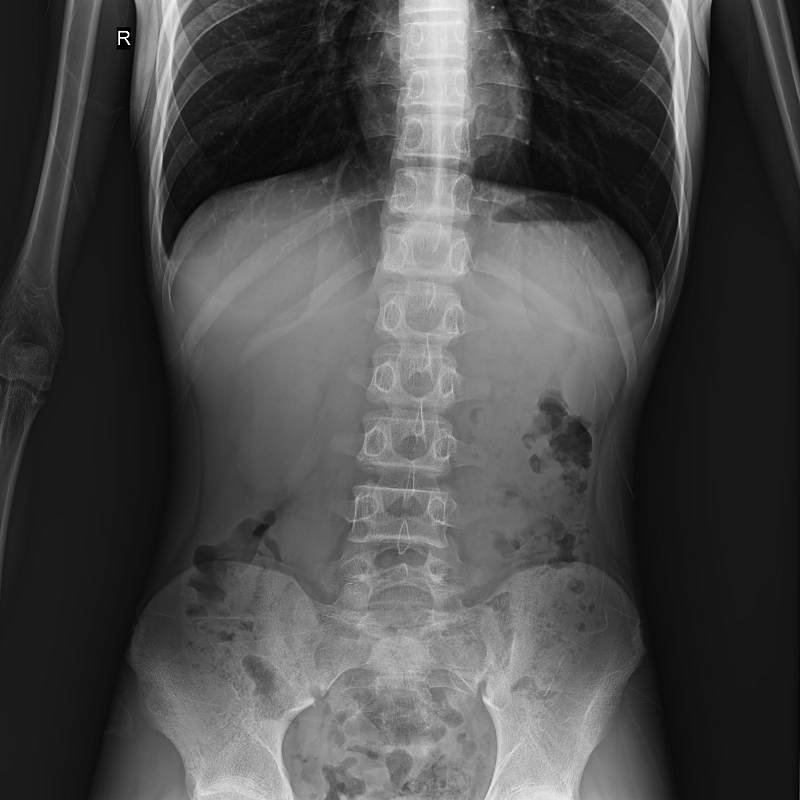

●呈現全下肢或全脊柱圖像

●在脊柱及下肢畸形矯正手術(shù)治療中,為術(shù)前方案制定和術(shù)后復查提供精準測量

●有效解決傳統X光片不能一次成像問(wèn)題,為患者提供更加優(yōu)質(zhì)的醫療服務(wù)